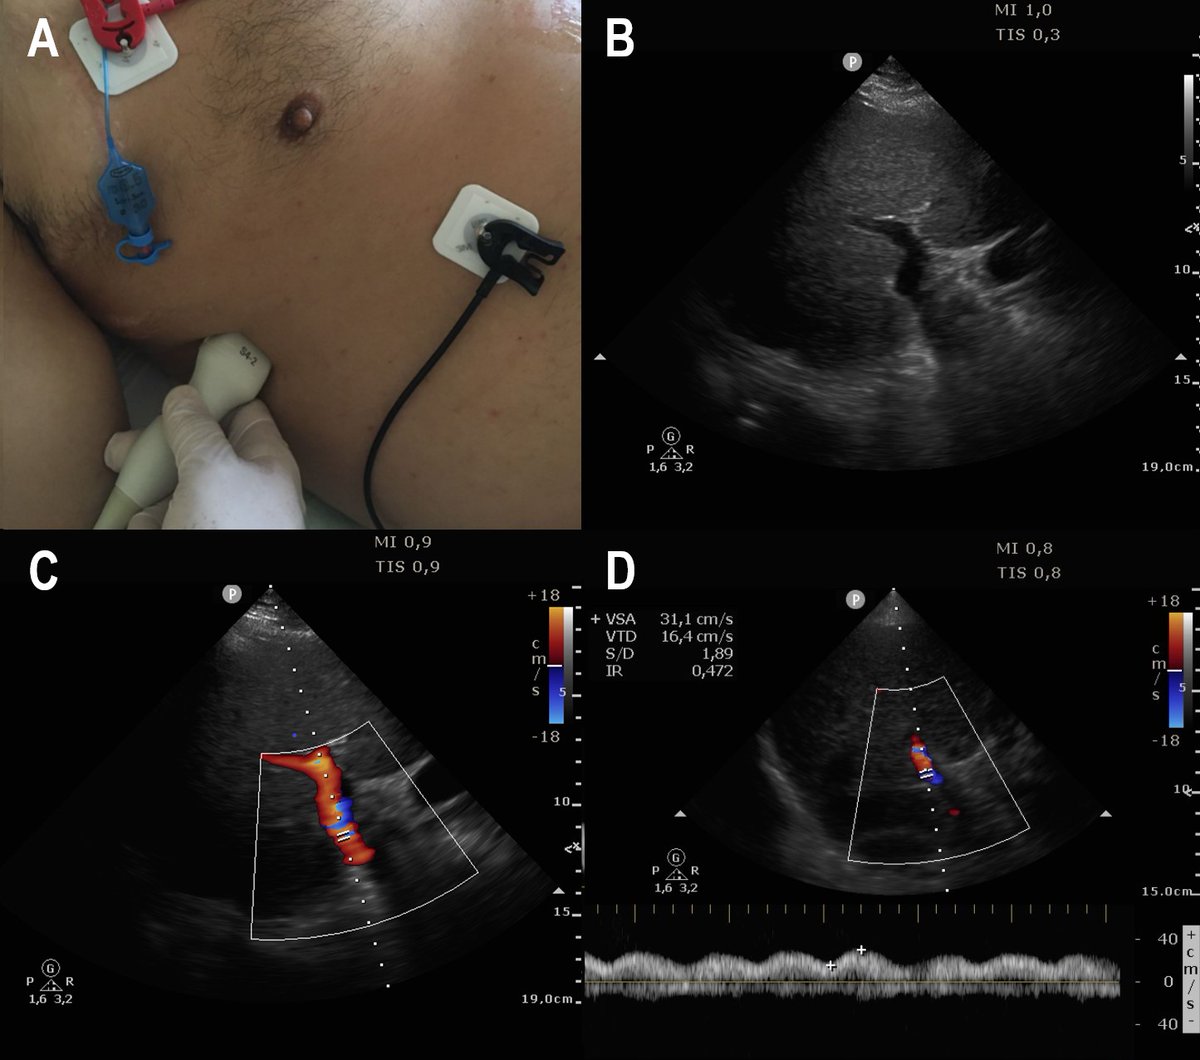

Dx Meningitis Bacteriana + HSA GCS 3/15 midriasis arreactiva, sin reflejos de tronco, test de apnea abortado por bradicardia. EEG no disponible Hilo completo desde... twitter.com/matibriz/statu… @Issac80 @ABCDEcografia @JuanFolco @ASARUC1